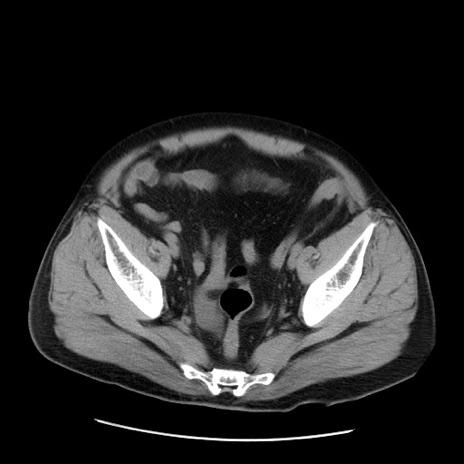

症例20(横断像)

【症例】 60歳代男性

【主訴】 腹部膨満、嘔吐

【現病歴】5日前頃より倦怠感を認め食事量減少し4日前の朝嘔吐、食事摂取困難となった。 3日前近医受診し点滴施行され整腸剤などを処方された。 当日他院を受診し、腹部膨満著明、炎症反応の上昇(CRP10.8、WBC11200)あり、紹介受診となる。

【身体所見】 意識JCS1 受け答えがはっきりしないBP 111/57mHg、 P 67bpm、、BT35.2°C、SpO2 97%(RA)、 腹部:膨隆、打診で鼓音あり、全体的に圧痛有り、腸蠕動音(-)、反跳痛ははっきりせず。

【データ】WBC 11400、CRP 14.20